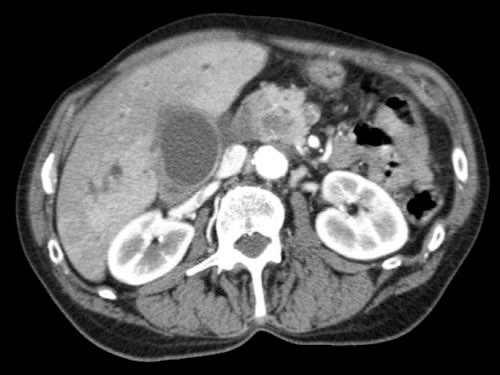

Đánh giá giai đoạn tại chỗ cần được thực hiện bằng CT tụy chất lượng cao, bao gồm thì động mạch muộn và thì tĩnh mạch cửa.

Ung thư biểu mô tuyến tụy thường biểu hiện là một khối giảm tỷ trọng, kém mạch máu, được nhận thấy rõ nhất ở thì động mạch muộn. Đây cũng là thì tốt nhất để đánh giá giải phẫu động mạch nhằm phát hiện các biến thể và hẹp mạch.

Thì tĩnh mạch cửa là tốt nhất để phát hiện di căn gan cũng như phát hiện hẹp và xâm lấn tĩnh mạch.